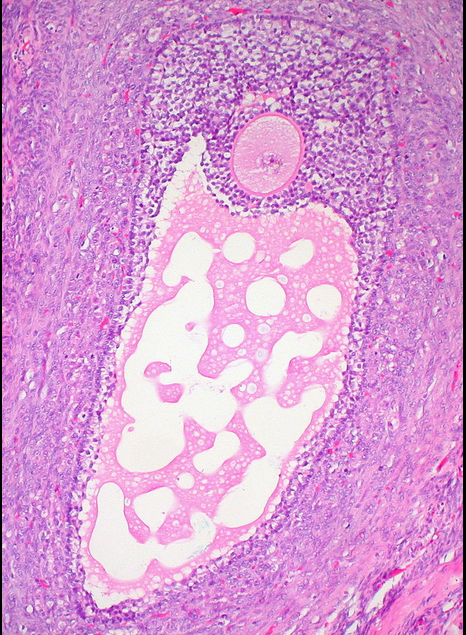

What are ovarian follicles? When can they become clinically relevant?

In females, the invaginating cords of coelomic epithelium (serosa) break apart into vesicular spheres called ovarian follivles, each of which initially contain multiple germ cells. Most of these are located around the margin of the indifferent gonad. All of the mesonephric tubules degenerate, as a result, the follicles fill the entire ovary. The mesonephric ducts largely degenerate in females, though nonfunctional remnants are occasionally found near the ovary and the urogenital sinus. These can be of clinical consequence if they become cystic.